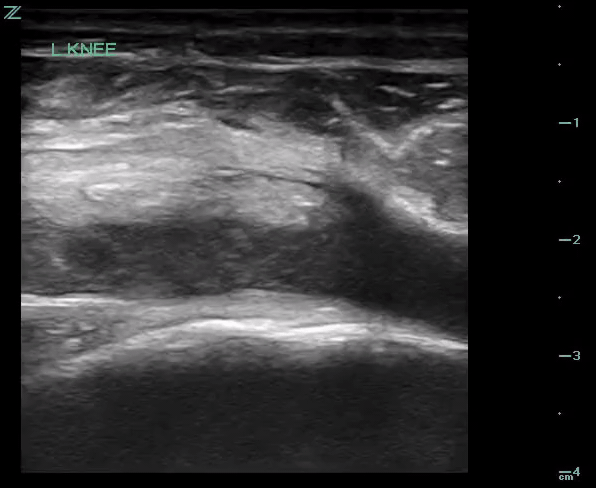

POCUS of the left knee was performed, which was concerning for a patellar tendon rupture and a joint effusion. (Figure 1 and Video 1) In addition, there was posterior acoustic shadowing obscuring part of the patellar tendon concerning for an avulsed bony fragment. (Figure 2) X-rays were performed, which confirmed the suspected diagnosis of a left tibial tubercle avulsion. (Figure 3) The patient was ultimately taken to the operating room for an Open Reduction and Internal Fixation (ORIF) by Orthopedic Surgery and discharged home the following day in a knee brace.

Figure 2. Patellar tendon with focus of acoustic shadowing (arrow) concerning for avulsed bony fragment (*)

In our case report, we successfully identified key features suggestive of tibial tubercle fractures: disruption of the patellar tendon, posterior acoustic shadowing of a bone fragment, and a large joint effusion. To perform knee ultrasound, the linear probe should be used and placed inferior to the patella in sagittal plane. The patellar tendon should be visualized in two planes, fanning through it completely (Video 1), and compared to the contralateral normal knee. (Figure 4) Abnormal findings suggestive of epiphyseal fractures include disruption of the tendon, an increased hypoechoic space adjacent to or posterior to the tendon (suggestive of either hemarthrosis or a hematoma), or a hypoechoic zone (ie, posterior acoustic shadowing due to an avulsed bony fragment).3,4